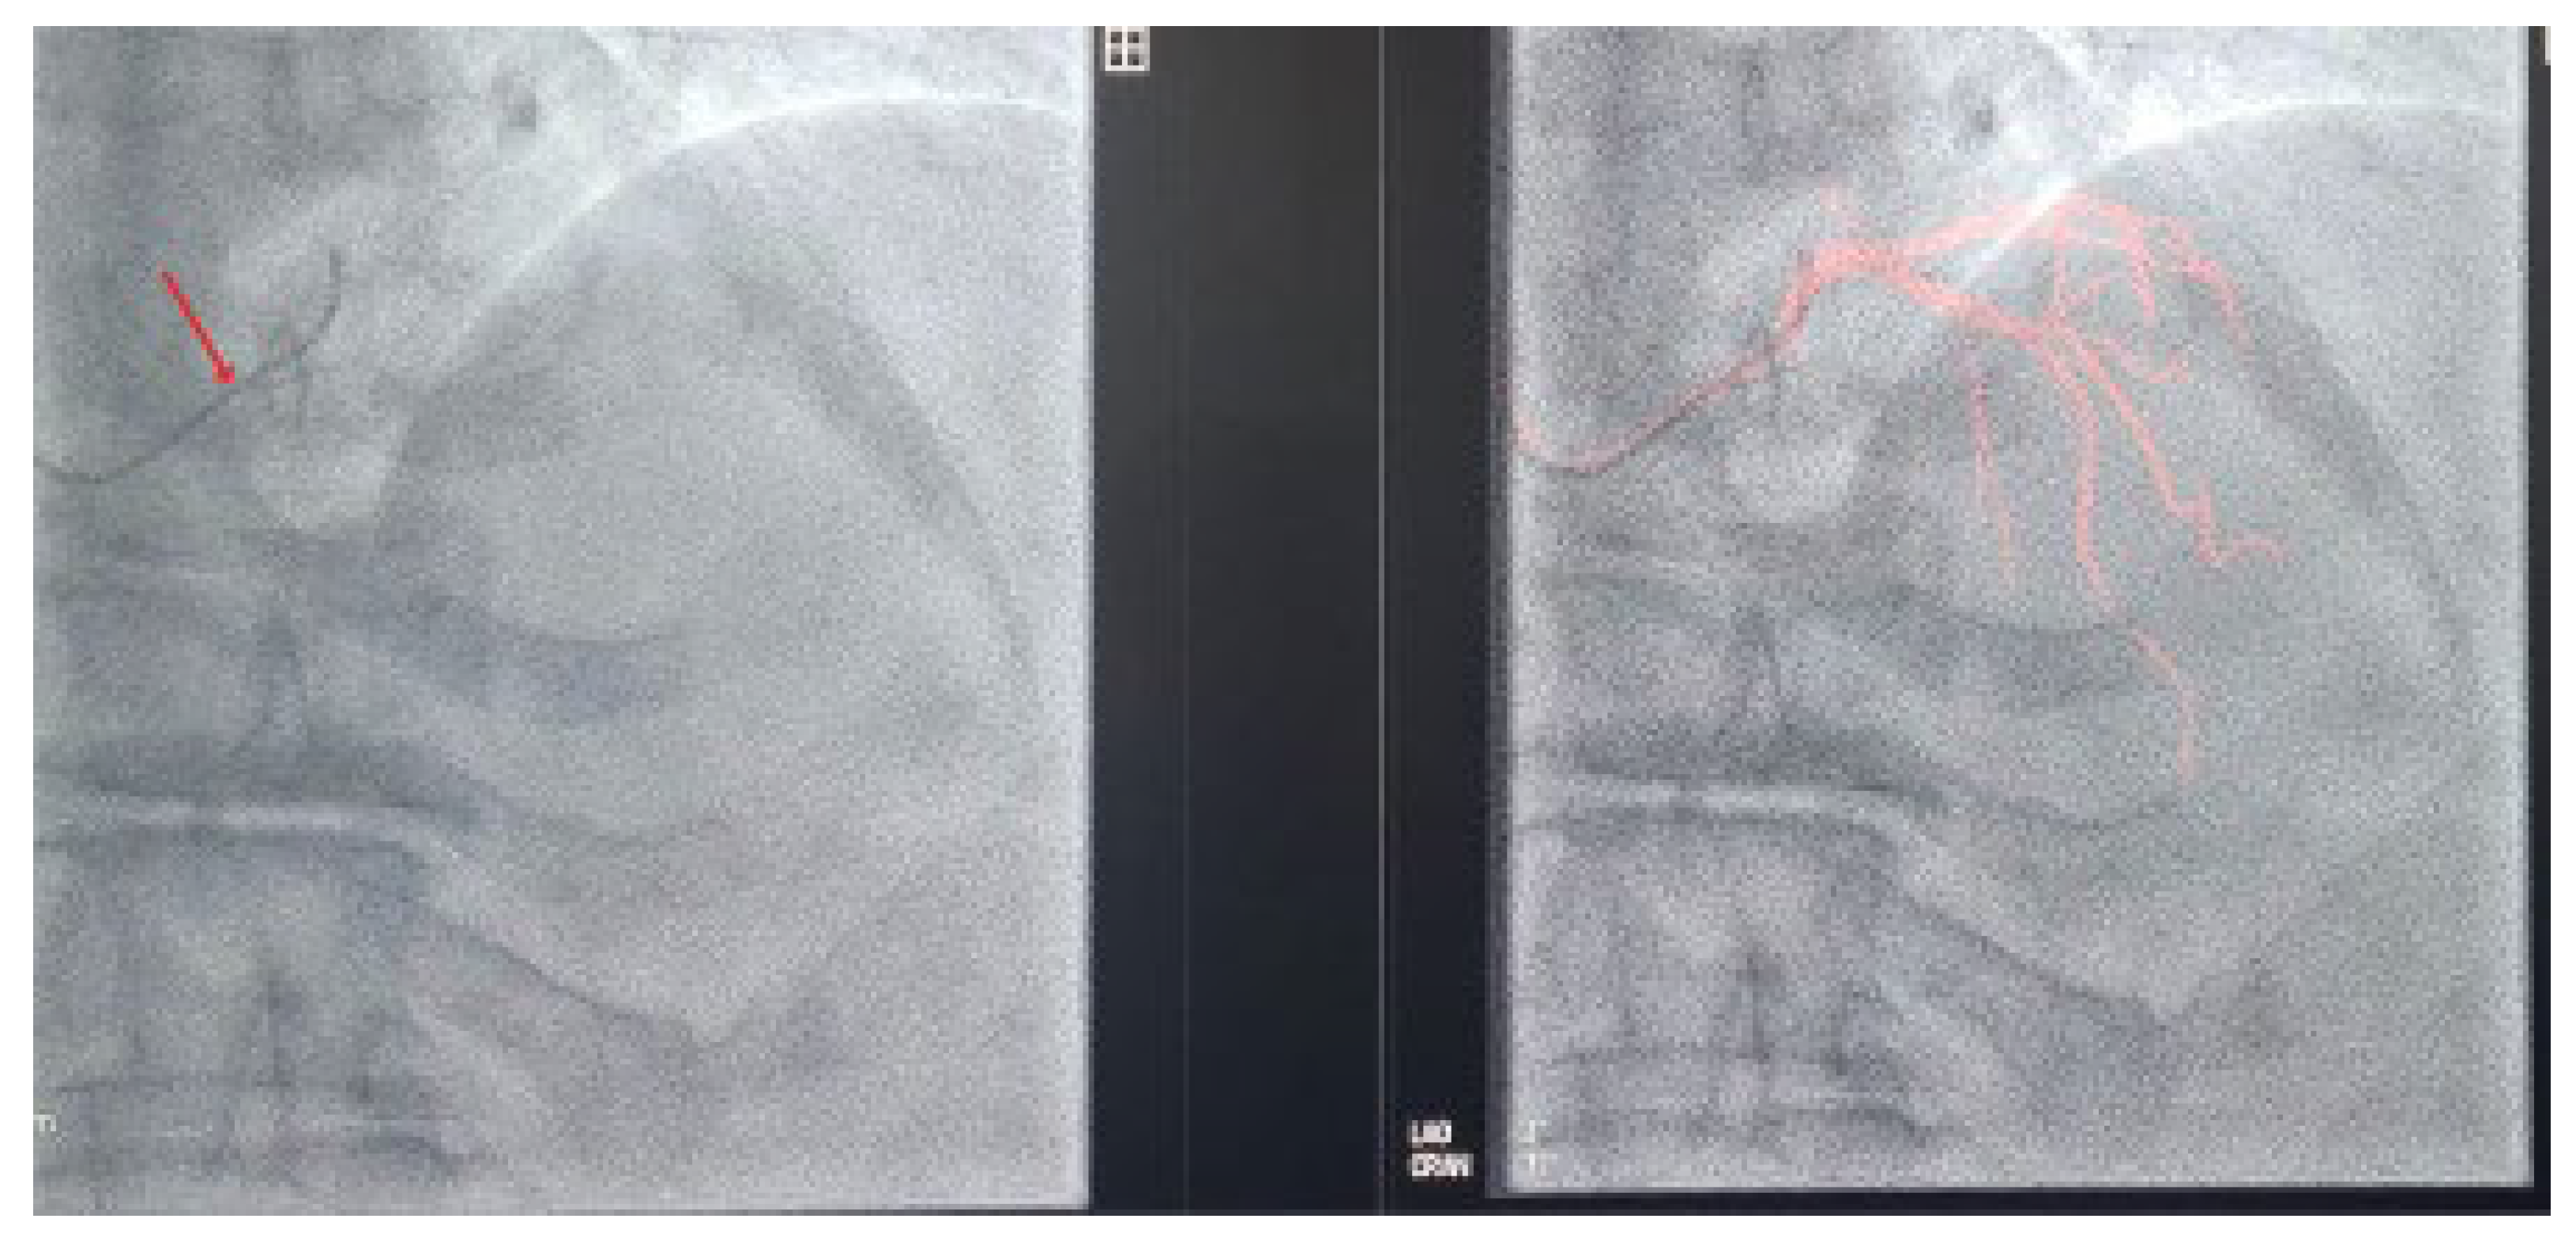

To address these challenges, adjunctive imaging modalities have been adapted to enable ultra-low contrast PCI. Intravascular ultrasound (IVUS) provides detailed cross-sectional images without reliance on contrast media (Figure 1) and is recommended in complex interventions [5,6]. OCT provides high-resolution plaque characterisation and stent assessment (Figure 2), but requires flushing, typically with contrast media; however, substitutes such as low-molecular-weight dextran and heparinised saline have shown promise as alternatives [51,52,53,54]. DCR software overlays a live coronary roadmap onto the fluoroscopic image, enabling navigation of coronary tools and stent delivery without repeated contrast injections (Figure 3) [7,55]. While these modalities provide valuable anatomical information, they remain dependent on fluoroscopic platforms and do not eliminate contrast use entirely, highlighting the potential role for complementary navigation technologies such as EAMS.

Figure 1. Multi-plane illustration of right coronary artery (RCA) assessment: (A) Coronary angiogram showing multiple areas of stenosis, with one marked by an arrow. (B) IVUS image demonstrating a fibrocalcific plaque in the mid RCA (arrow). (C) IVUS image showing a 360° arc of calcium in the RCA, with the arrow highlighting the calcification.